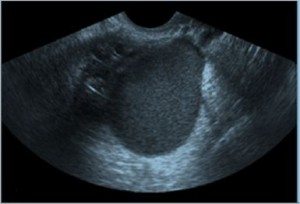

Kadınların rahim kisti olmalarının sebeplerinden en önemlisi hormonlarında olan değişimlerdir. Bu süreç aslında rahmin gebeliğe hazırlık sürecidir. Rahimde kist neden oluşur. Bu yumurtalıkların büyüyüp birçok küçük kist içerdiği bir bozukluktur.

Bunun yanında bir çok farklı sebeplerde söz konusudur. Rahimde kist patlaması rahimde bulunan kistin fazla büyümesi sonucunda içerisinde bulunan sıvının artışına veya yırtılıp sıvının dağılmasına rahimde kist patlaması adı verilir. Kist zaman içinde büyüyebileceği gibi küçülerek kaybolabilir fakat kaybolan kist yeniden tekrarlayabilir. Düzenli olarak yumurtlamayan kadınlar çoğul kistler geliştirebilirler.